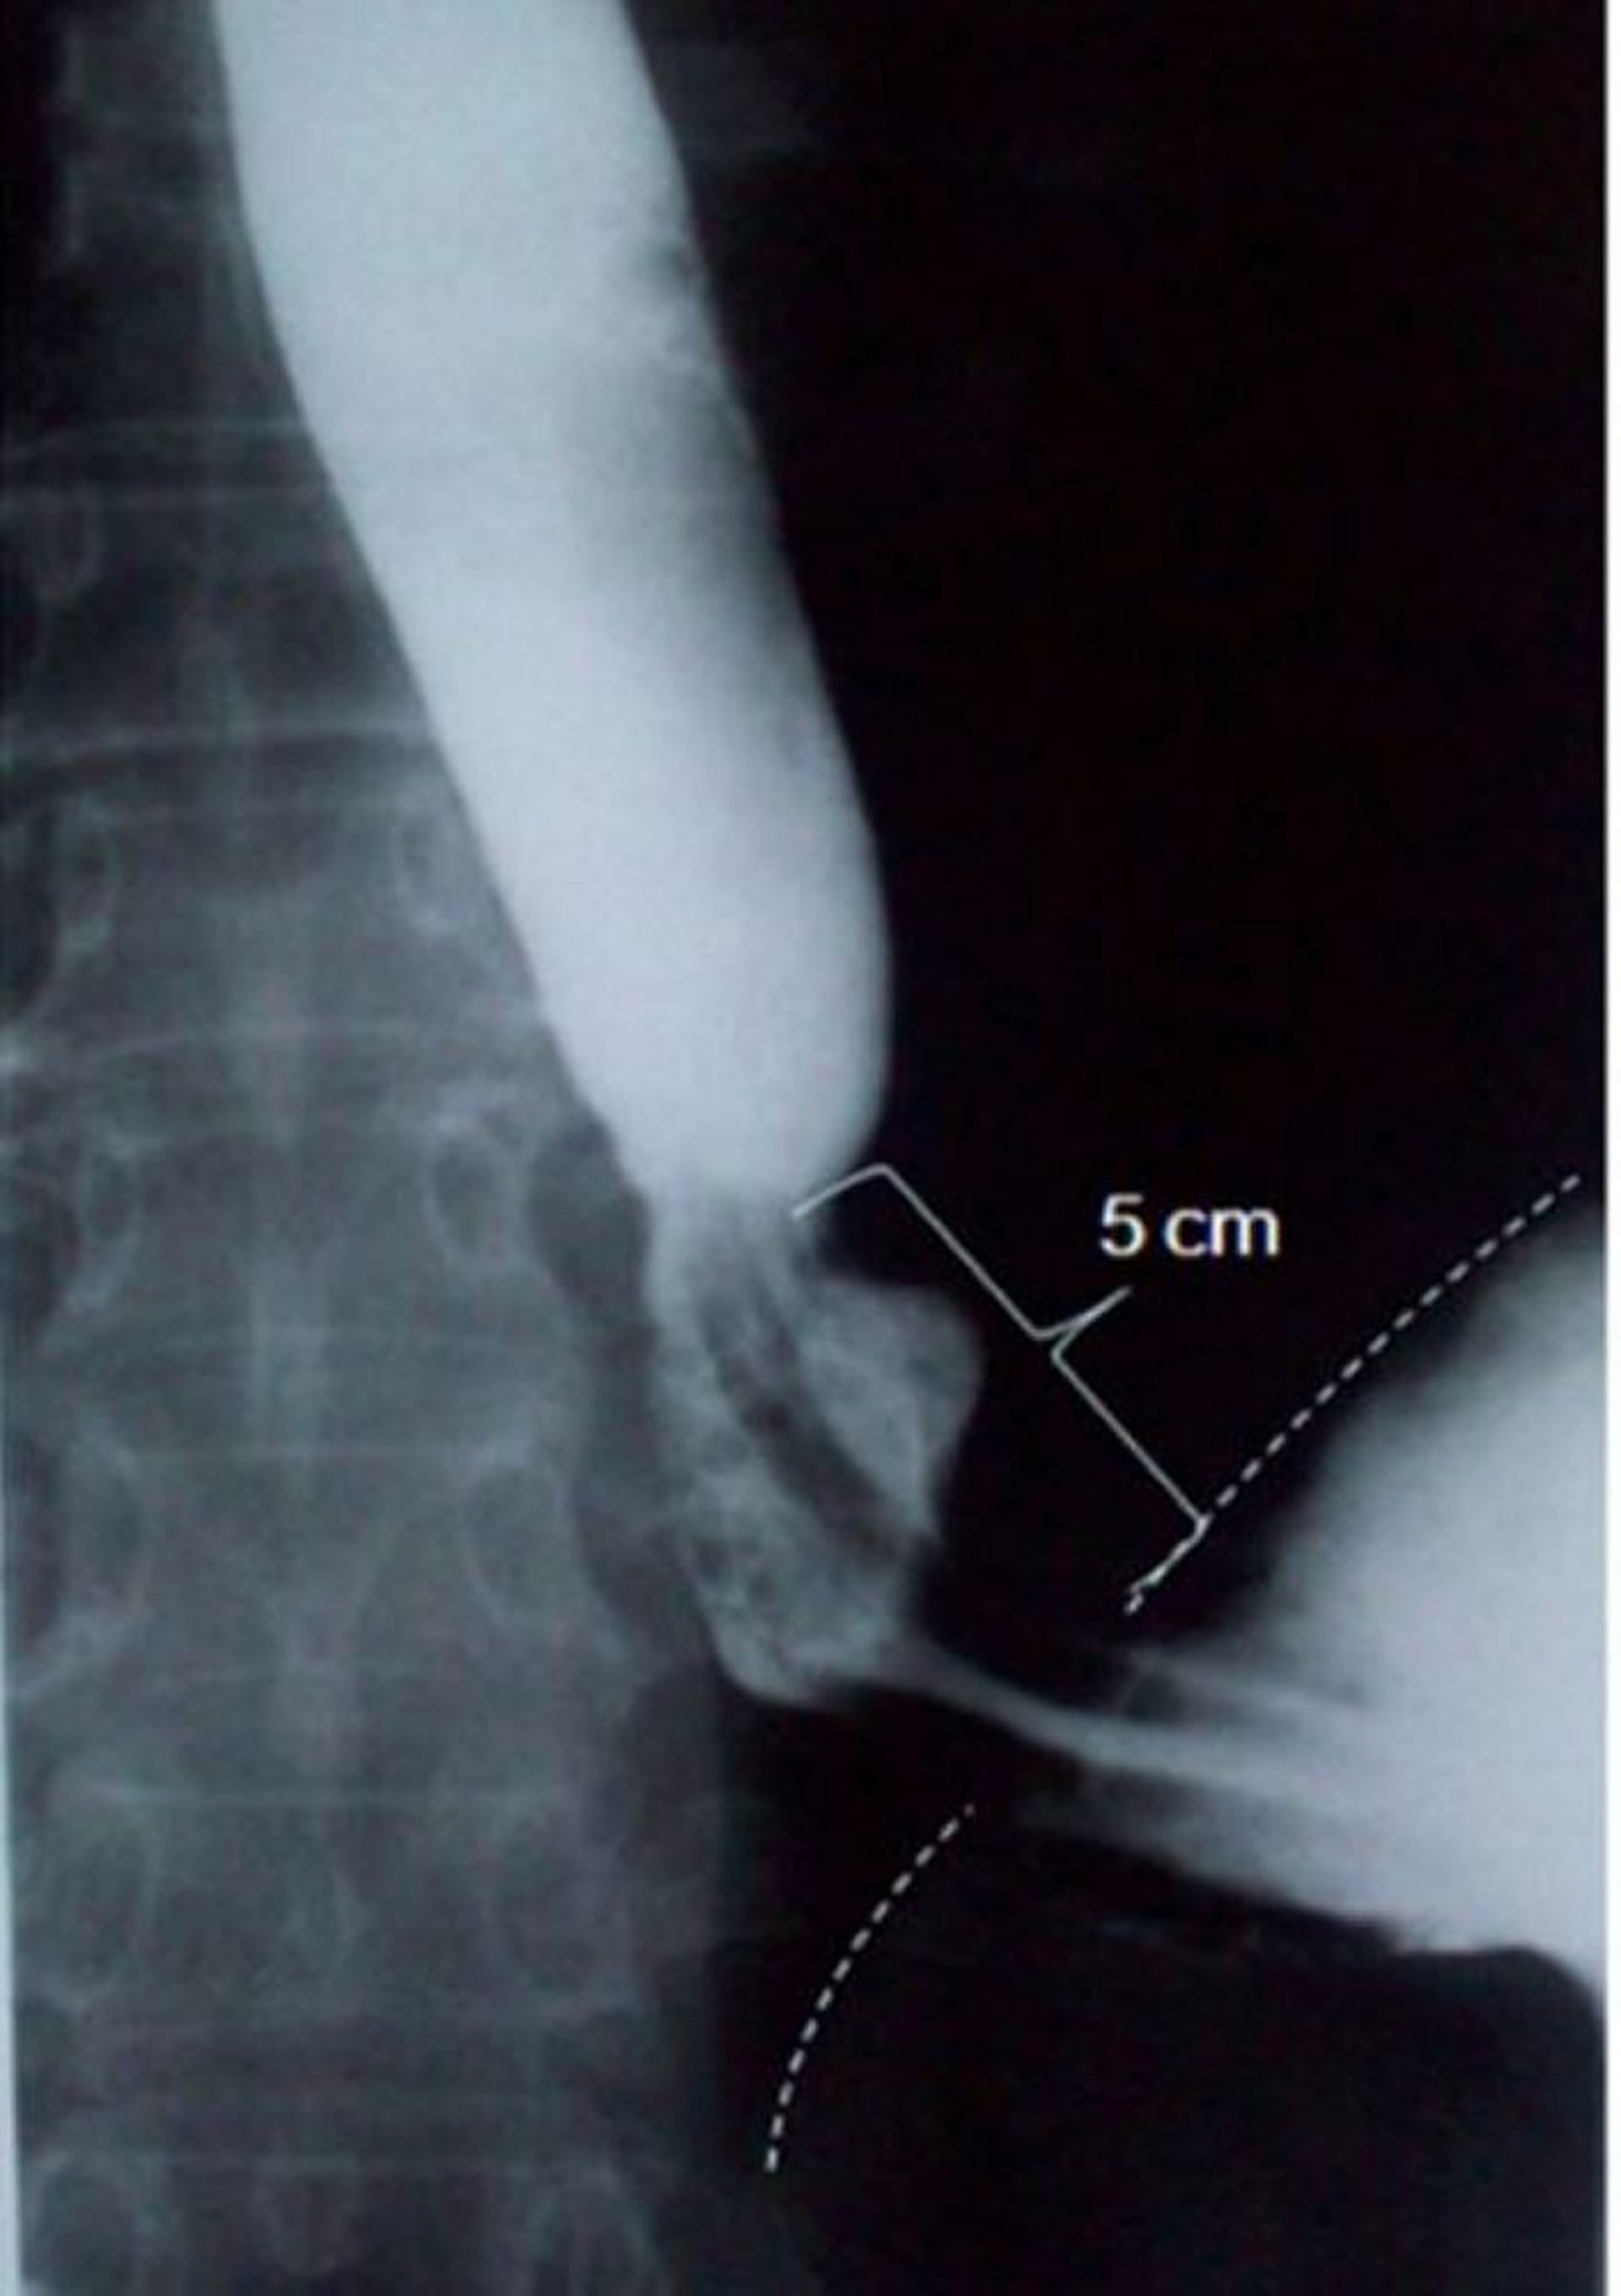

Исследование с помощью бариевой взвеси: скользящая грыжа пищеводного отверстия диафрагмы

На этом изображении показана скользящая грыжа пищеводного отверстия диафрагмы размером 5 сантиметров (5 см) в осевом направлении (пунктирная линия указывает на край диафрагмы).